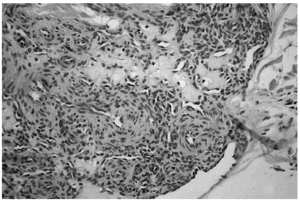

Se realizó una extirpación quirúrgica de la lesión. El estudio histopatológico mostró una tumoración dérmica multilobulillar con una zona central hipocelular, esclerosa y otra hipercelular en la periferia en la que se veían multiples espacios vasculares (fig. 2). Estas áreas más periféricas de espacios vasculares ramificados recordaban a un hemangipericitoma, y se continuaban insensiblemente con nódulos esclerosos. También se observaban nódulos hemangiopericitoides a distancia y sin conexión aparente con la tumoración principal (fig. 3).

Fig. 2.--Panorámica del tumor situado en dermis, con áreas esclerosas hipocelulares junto a otras hipercelulares. Destaca la presencia de hendiduras vasculares en la periferia de algunos nódulos.